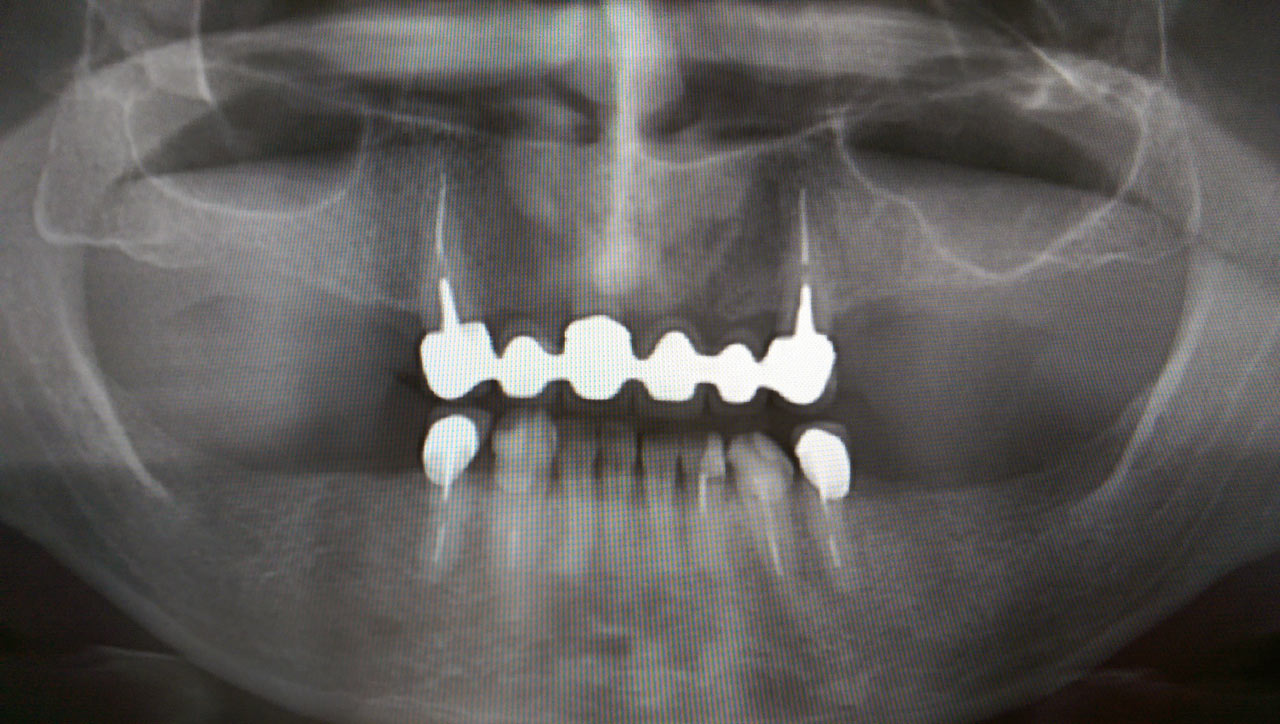

Alsó állcsont teljes rehabilitációja 72 óra alatt

Alsó állcsont teljes rehabilitációja 72 óra alatt, azonnal terhelhető implantátumokkal súlyos paradontitisben szenvedő dohányzó páciens esetében. Az alsó állcsont fogai mind mozogtak az előrehaladott fogágypusztulás miatt.

A fogakat eltávolítottuk, a gyulladt, fertőzött csontot kitakarítottuk, kifertőtlenítettük, majd azonnal implantáltunk.

Svájci, IHDE márkájú, azonnal terhelhető implantátumokat helyzetünk be, és ezekre harmadnapra rögzített, hosszútávú, fémvázas, esztétikus műanyaggal leplezett hidat ragasztottunk be.

Ezt az ideiglenes hidat a sebek gyógyulása miatt használjuk, de tartóssága miatt véglegesként is használható.

A legtöbb esetben, ahogy itt is, 6 hónap múlva porcelán hídra cseréljük, a teljes gyógyulás után.